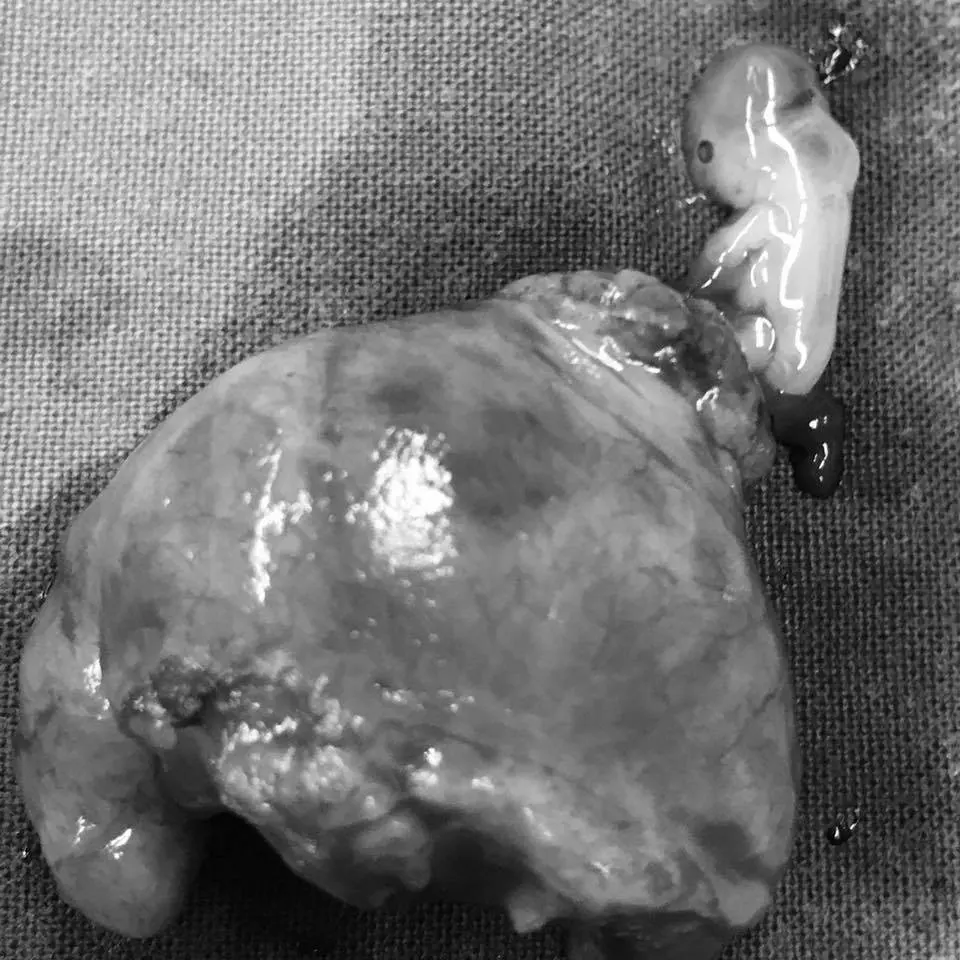

จากประสบการณ์การดูแลคนไข้ บ่อยครั้งผมได้ดูแลสตรีตั้งครรภ์ที่ประสบปัญหาตั้งครรภ์นอกมดลูก ซึ่งเป็นภาวะที่ค่อนข้างอันตราย และในคนไข้บางรายอาจโชคร้าย ความรุนแรงจากการเสียเลือดอาจนำไปสู่การเสียชีวิตเลยนะครับ

แต่ในบางกรณี ที่ตัวอ่อนฝังตัวในตำแหน่งอื่นที่ไม่ใช่ โพรงมดลูก ทางการแพทย์เรียกว่า การตั้งครรภ์นอกมดลูก ซึ่งตำแหน่งของการฝังตัวที่ผิดปกตินี้อาจจะเกิดที่ท่อนำไข่ ที่รังไข่ ที่เยื่อบุช่องท้อง ที่ปากมดลูก เป็นต้น ทั้งหมดนี้ถือเป็นการฝังตัวที่ ผิดที่ผิดทาง และทารกจะไม่สามารถเติบโตแบบทารกปกติทั่วไปได้นะครับ ,

เนื่องจากตำแหน่งที่ตัวอ่อนไปฝังตัวผิดที่ผิดทาง อวัยวะนั้นจะมีความบอบบาง ไม่สามารถขยายขนาดสำหรับการเติบโตของทารกได้ จึงมักเกิดการแตกหรือ การฉีกขาดของอวัยวะที่ตัวอ่อนไปฝังตัว จนทำให้คนไข้ตกเลือดในช่องท้องอย่างมากมาย

การตั้งครรภ์นอกมดลูก มีแนวทางการดูแลรักษาหลายวิธี ขึ้นอยู่กับดุลพินิจของแพทย์ผู้ดูแลนะครับ เท่าที่มีในปัจจุบัน ขออธิบายง่ายๆ ว่า

2.รักษาด้วยการผ่าตัดทั้งแบบมาตรฐานและผ่าตัดผ่านกล้อง